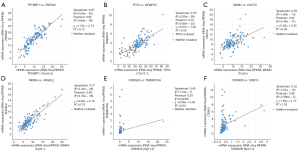

Different mutation types may have distinct biological functions in various cancers, and the co-expression of genes may also affect gene functions. Using the cBioPortal database, we explored the location and types of mutation, as well as co-expression, among genes related to the TP53 signaling pathway. Among these genes, TP53 (2.3%) was the most frequently aberrant gene in WT, followed by MDM4 (0.8%), and then MDM2 and TP53BP1 (0.2%). The most common types of mutation in TP53 were missense and deep deception, while amplification was the most common mutation in MDM2, MDM4, and TP53BP1 (Figure 3A,B). The three-dimensional structure of TP53 is shown in Figure 3C.

The location of mutations in TP53 are shown in Figure 4. The significant co-expressed genes in the TP53 signaling pathway included ZNF609 (zinc finger protein 609), WRAP53 (WD40-encoding RNA antisense to p53), CNOT2 (CC chemokine receptor 4-negative regulator of transcription 2), ANGEL2, TMEM255A, and CDH13 (cadherin 13) (Figure 5). Further, we investigated the relationships of the mutation types (Figure 6), copy number alterations (CAN, Figure 7), and methylation (Figure 8) with the expression levels of defined genes. The gene expression levels were negatively correlated with methylation, but the CNA and mutated type did not have a significant influence. Figure 9 shows the relationship between the genes in the TP53 signaling pathway.